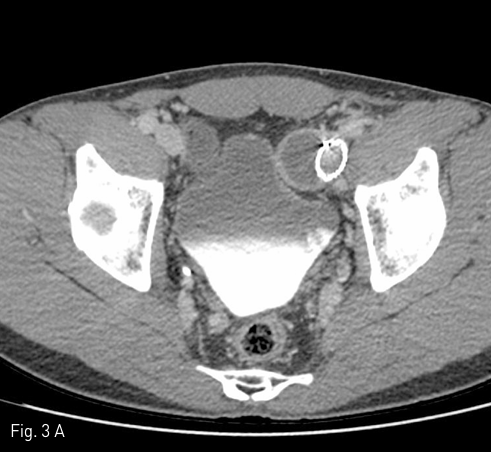

좌측 오금 정맥을 초음파 유도하에 천자한 후, 7-Fr long sheath (Destination, Terumo, New Jersey, USA)를 삽입하고, 5-Fr 도관을 좌측 외장골 정맥 원위부에 위치시켜 혈관 조영술을 시행하였다. 좌측 외장골 정맥류의 위치를 확인하고, 12-Fr long sheath (Flexor, Cook, Indiana, USA)로 교체하여 14.5 mm X 10 cm 와 14.5 mm X 7 cm 크기의 스텐트-그라프트 (Excluder, Gore, Arizona, USA)를 충분히 겹쳐서 위치시키고, 14 mm X 4 cm 풍선카테터를 이용하여 확장시켰다. 시술 후 외장골 정맥의 aneurysm 내로 조영제의 누출이 없음을 확인하고 시술을 마쳤다. (Fig. 2)

Fig 2

After stent-graft placement, venography shows successful exclusion of aneurysm from the left external iliac vein.